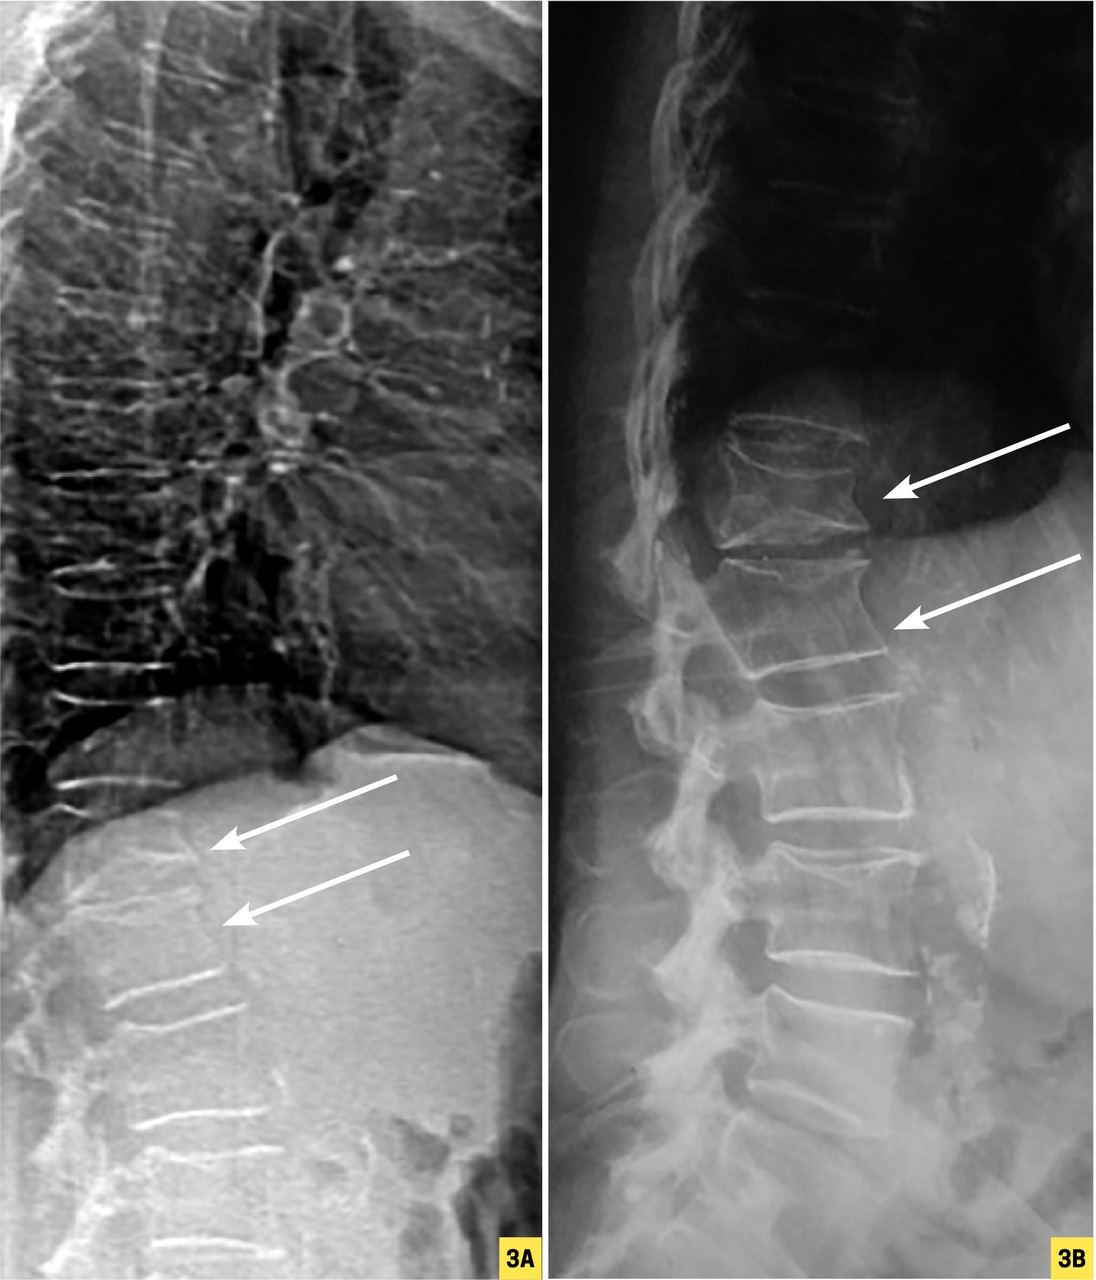

Depuis 10 ans , les appareils de densitométrie sont capables de produire une image de face et de profil du rachis lombaire et thoracique grâce à une technique appelée VFA (Vertebral Fracture Assessment, fig. 3). Ces images n’ont pas la qualité d’un cliché radiographique mais peuvent révéler une grande partie des fractures vertébrales, soit un apport diagnostique majeur. Toutefois, ces dernières doivent être confirmées par une radiographie standard (qui permet aussi de vérifier l’absence d’ostéolyse ou de recul du mur postérieur).